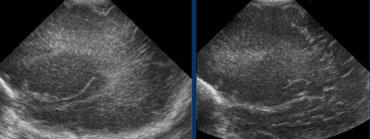

TRÁI: Hình ảnh khảo sát ban đầu cho thấy flaring. PHẢI: Hình ảnh tái khám sau một tuần cho thấy chất trắng quanh não thất bình thường.

Cần theo dõi tái khám để phân biệt flaring với PVL độ I.

Trường hợp bên trái minh họa một trẻ sinh non có hình ảnh flaring.

Tại lần tái khám, không ghi nhận sự hình thành nang và sau tuần đầu tiên, chất trắng quanh não thất trở về hình ảnh bình thường.